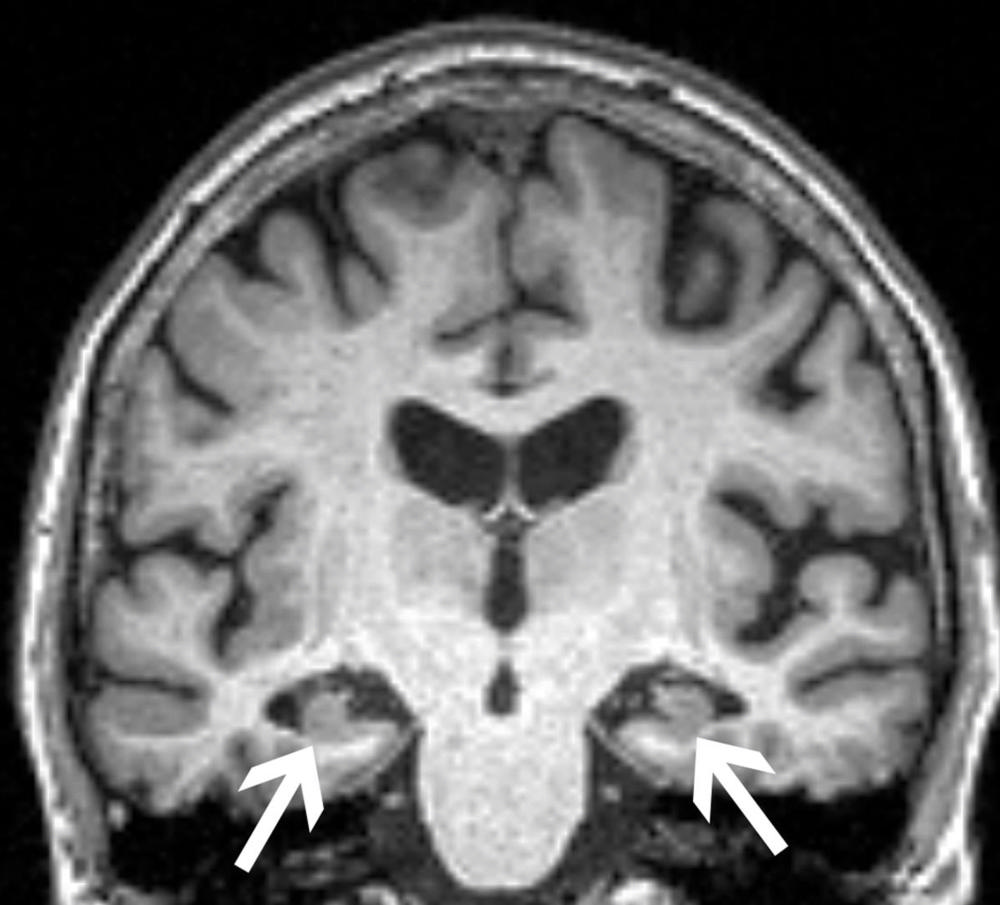

The researchers obtained brain MRIs to determine the baseline volumes of the hippocampus and the entorhinal cortex, two areas important to forming memories. They also tested for the presence of the ApoE4 allele, the most prevalent genetic risk factor for Alzheimer’s disease. Anxiety was measured with established clinical surveys.

As expected, patients who progressed to Alzheimer’s disease had significantly lower volumes in the hippocampus and the entorhinal cortex and greater frequency of the ApoE4 allele. Most notably though, the researchers found that anxiety was independently associated with cognitive decline.

Figure 1. Brain MRI of a 72-year-old woman shows loss of volume of the hippocampus (arrows). The patient had all three characteristics, volume loss of the hippocampi, APOE4, and anxiety, found in the study to be associated with progression from mild cognitive impairment to dementia.